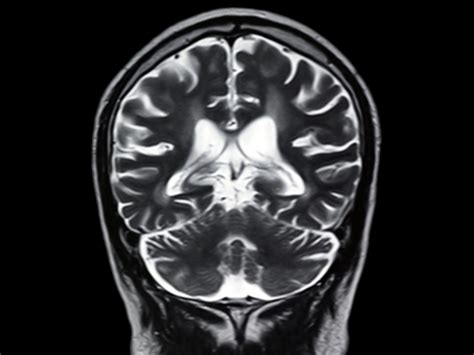

Medical imaging technology has revolutionized the way we understand human health, and among these diagnostic tools, Brain MRI Images stand out as the gold standard for visualizing the complex architecture of the central nervous system. Magnetic Resonance Imaging (MRI) provides incredibly detailed, non-invasive views of the brain's internal structures, allowing medical professionals to identify anomalies, track the progression of diseases, and plan surgical interventions with pinpoint accuracy. Unlike X-rays or CT scans, which rely on ionizing radiation, MRI machines utilize powerful magnetic fields and radio waves to generate sophisticated, multi-planar cross-sections of brain tissue.

At its core, the process of capturing Brain MRI Images is a marvel of physics and engineering. When a patient enters the scanner, their body interacts with a strong magnetic field that causes the hydrogen protons in their body’s water molecules to align. Radiofrequency pulses are then applied, forcing these protons to shift their alignment. As the pulses are turned off, the protons return to their natural state, emitting radio signals that the MRI scanner detects and converts into high-resolution imagery.

This technology is essential for distinguishing between various types of tissues, such as gray matter, white matter, and cerebrospinal fluid. By manipulating the timing of the radiofrequency pulses—a process referred to as adjusting pulse sequences—radiologists can emphasize different pathological features, making it easier to spot tumors, lesions, or inflammatory processes.

Once the images are acquired, they are processed and sent to a radiologist. These specialists are trained to meticulously examine the Brain MRI Images, looking for subtle deviations from normal anatomy. They look for signals that are “hyperintense” (bright) or “hypointense” (dark) on the scan, which often indicate different types of pathology. The radiologist then synthesizes these findings into a comprehensive report for the referring physician, who uses the data to determine the next steps in treatment or management.